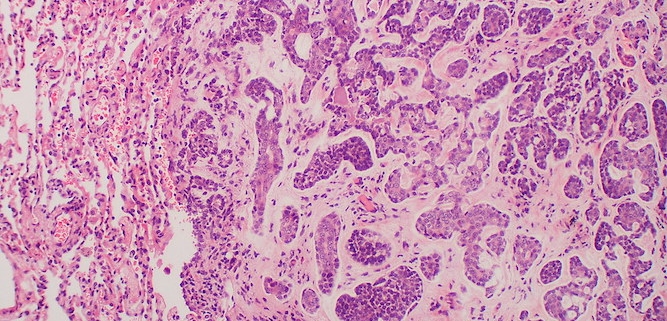

- Rakenne Epiteliaaliset kasvaimet muodostovat tyypillisesti tubuluksia, rauhasia ja solusaarekkeita, kun taas sukkulasoluiset kasvaimet muodostavat solujuosteita ja -pyörteitä. Pyörösoluisille kasvaimille on tyypillistä tasaisten solulaattojen ja -mattojen muodostaminen. Solukko voi myös olla löyhää tai tiivistä. Kasvaimen pahanlaatuisuuden kasvaessa usein myös kasvutapa muuttuu huonommin erilaistuneeksi eikä kasvainsolukko muodosta enää selviä, tunnistettavia rakenteita.

- Strooma Kasvaimen tukikudos eli strooma arvioidaan aina kasvaimia diagnosoitaessa. Tyypillisesti stroma koostuu sidekudoksesta ja verisuonista (ns. fibrovaskulaarinen strooma). Epiteliaalisilla kasvaimilla strooma on yleensä runsas ja mesenkymaalisilla kasvaimilla niukka. Pahanlaatuiset epiteliaaliset kasvaimet voivat stimuloida ympärilleen voimakasta strooman muodostusta, mitä kutsutaan desmoplasiaksi. Stroomaa ei kuitenkaan pidä sekoittaa mahdolliseen solujen väliaineeseen, jonka tuottaminen on monille mesenkymaalisille kasvaimille ominaista. Esimerkiksi luukasvaimet tuottavat osteoidia.